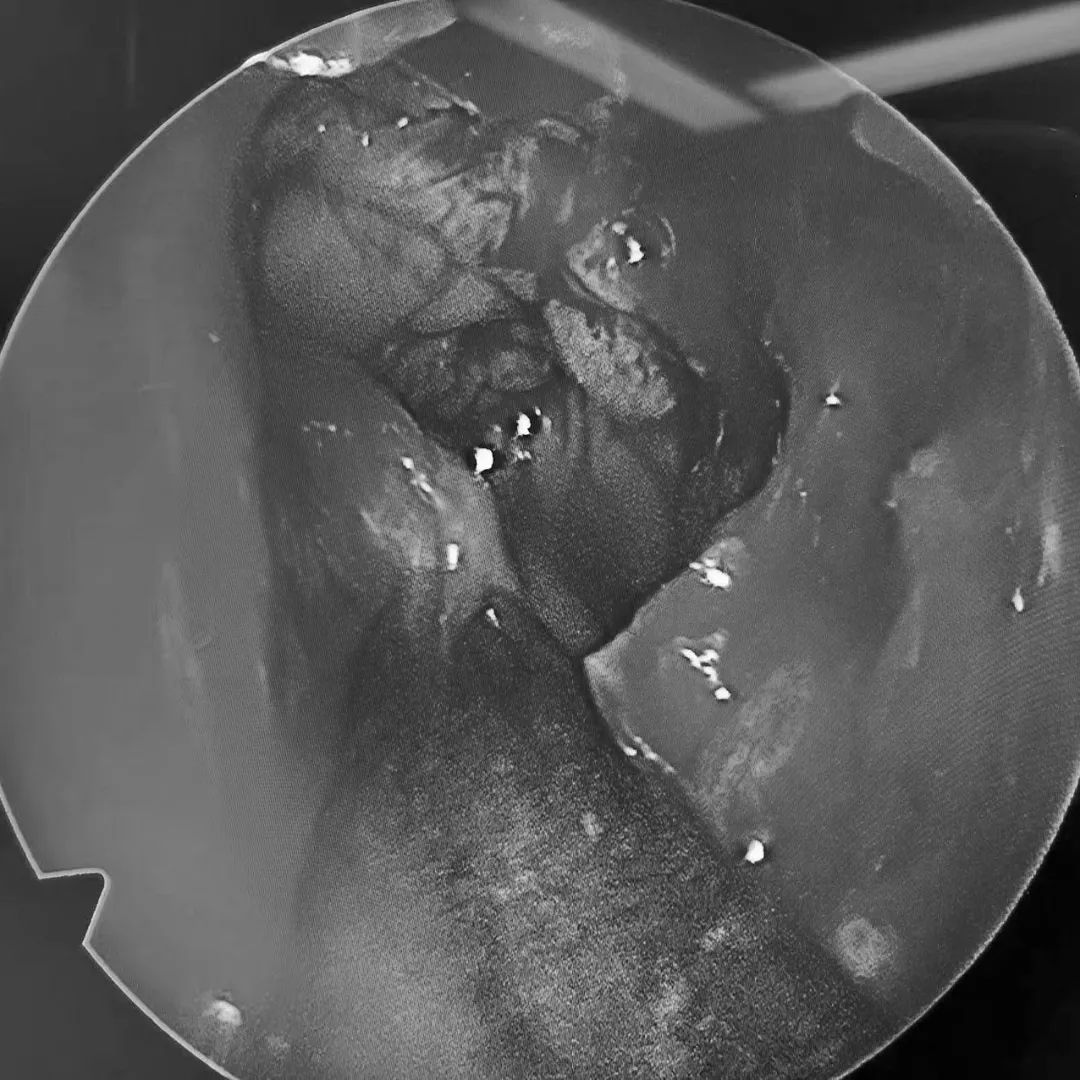

术中影像2

3月21日,耳鼻咽喉主任带领团队为其进行手术。术中,发现余女士的 鼻腔内的炎症已蔓延至上颌骨及眼眶内侧壁。 熊主任见状,立即清除蔓延部位的病变组织。